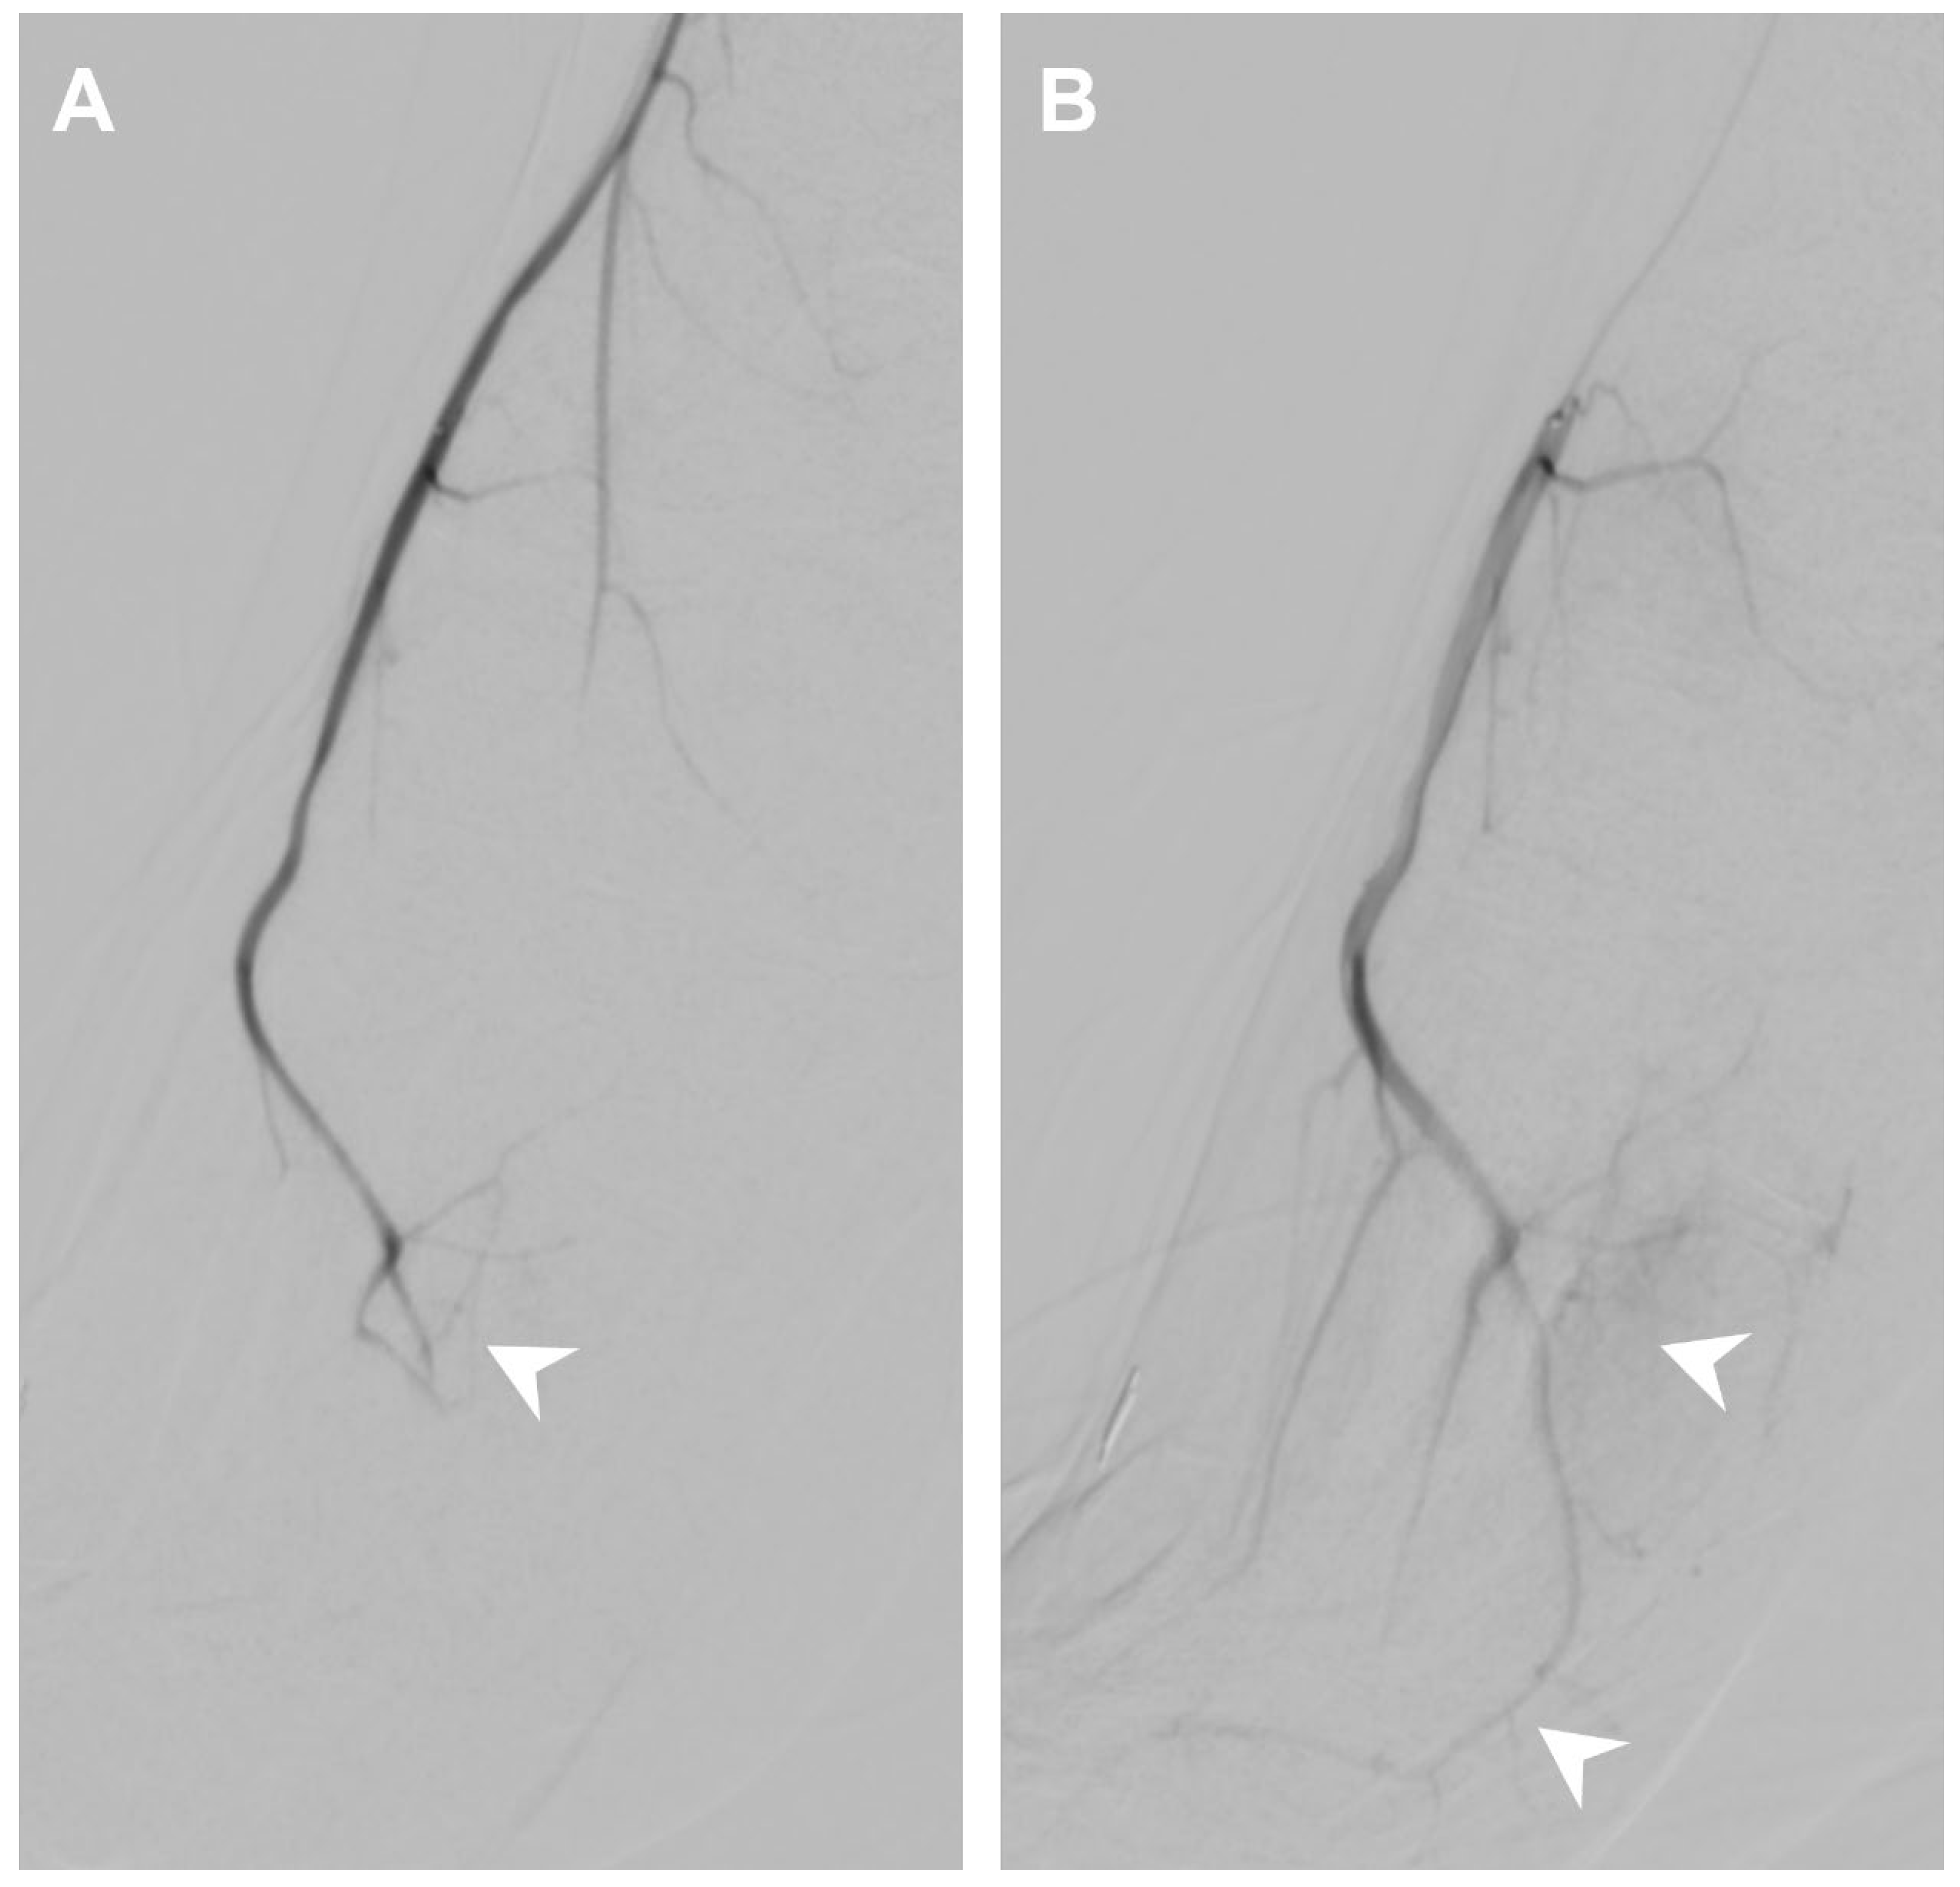

| Impaired distal perfusion | 6/7 (86%) | 0/7 (0) |

| Flow through anastomotic vessels | 3/7 (43%) | 1/7 (14%) |